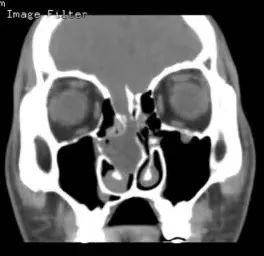

患者男,59岁,因左鼻腔涕中带血40余天入院,入院CT、MRI示前颅底肿瘤,侵犯前颅底骨质及硬脑膜。入院诊断:前颅底肿瘤。入院后在病房行活检示(左侧鼻腔)嗅神经母细胞瘤,排除手术禁忌症后行全麻下经鼻内镜下前颅底肿瘤及前颅底部分骨质磨除、硬脑膜切除,鼻颅底重建手术。

CT、MRI示前颅底肿瘤,侵犯前颅底骨质及硬脑膜